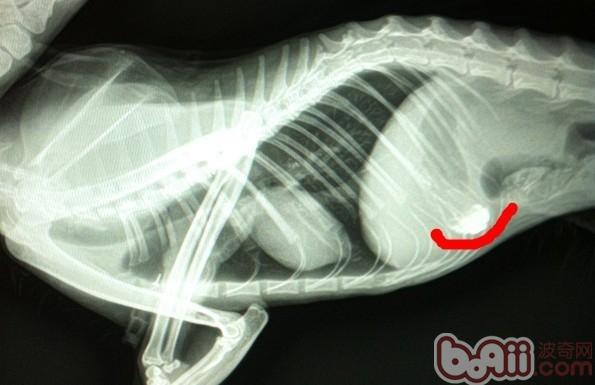

此為上文中提到的貓咪誤食的大閘蟹扎線,看似柔軟,但是這樣的線粗且長,經(jīng)過腸道蠕動(dòng)后更容易在腸道中堵塞,圖片中的線在鋇餐造影以后確定位置,手術(shù)治療,10天后貓咪逐漸恢復(fù)正常。

此片攝于患貓灌入鋇餐20小時(shí)后,正常情況下,鋇餐應(yīng)完全通過胃區(qū),通過腸道,應(yīng)幾乎排空,顯然此片中胃區(qū)任有少量殘余液體,腸道內(nèi)幾乎排空,反映出雖然消化道沒有完全堵塞,但胃排空較慢,腸道蠕動(dòng)減慢,因此貓為長毛貓,消瘦,主人常年在外缺乏管理,不能提供足夠的病情資料,與主人溝通后,采取保守治療,通過支持療法和食物緩瀉療法,此貓逐漸排除體內(nèi)伴有大量毛發(fā)的干燥積便。